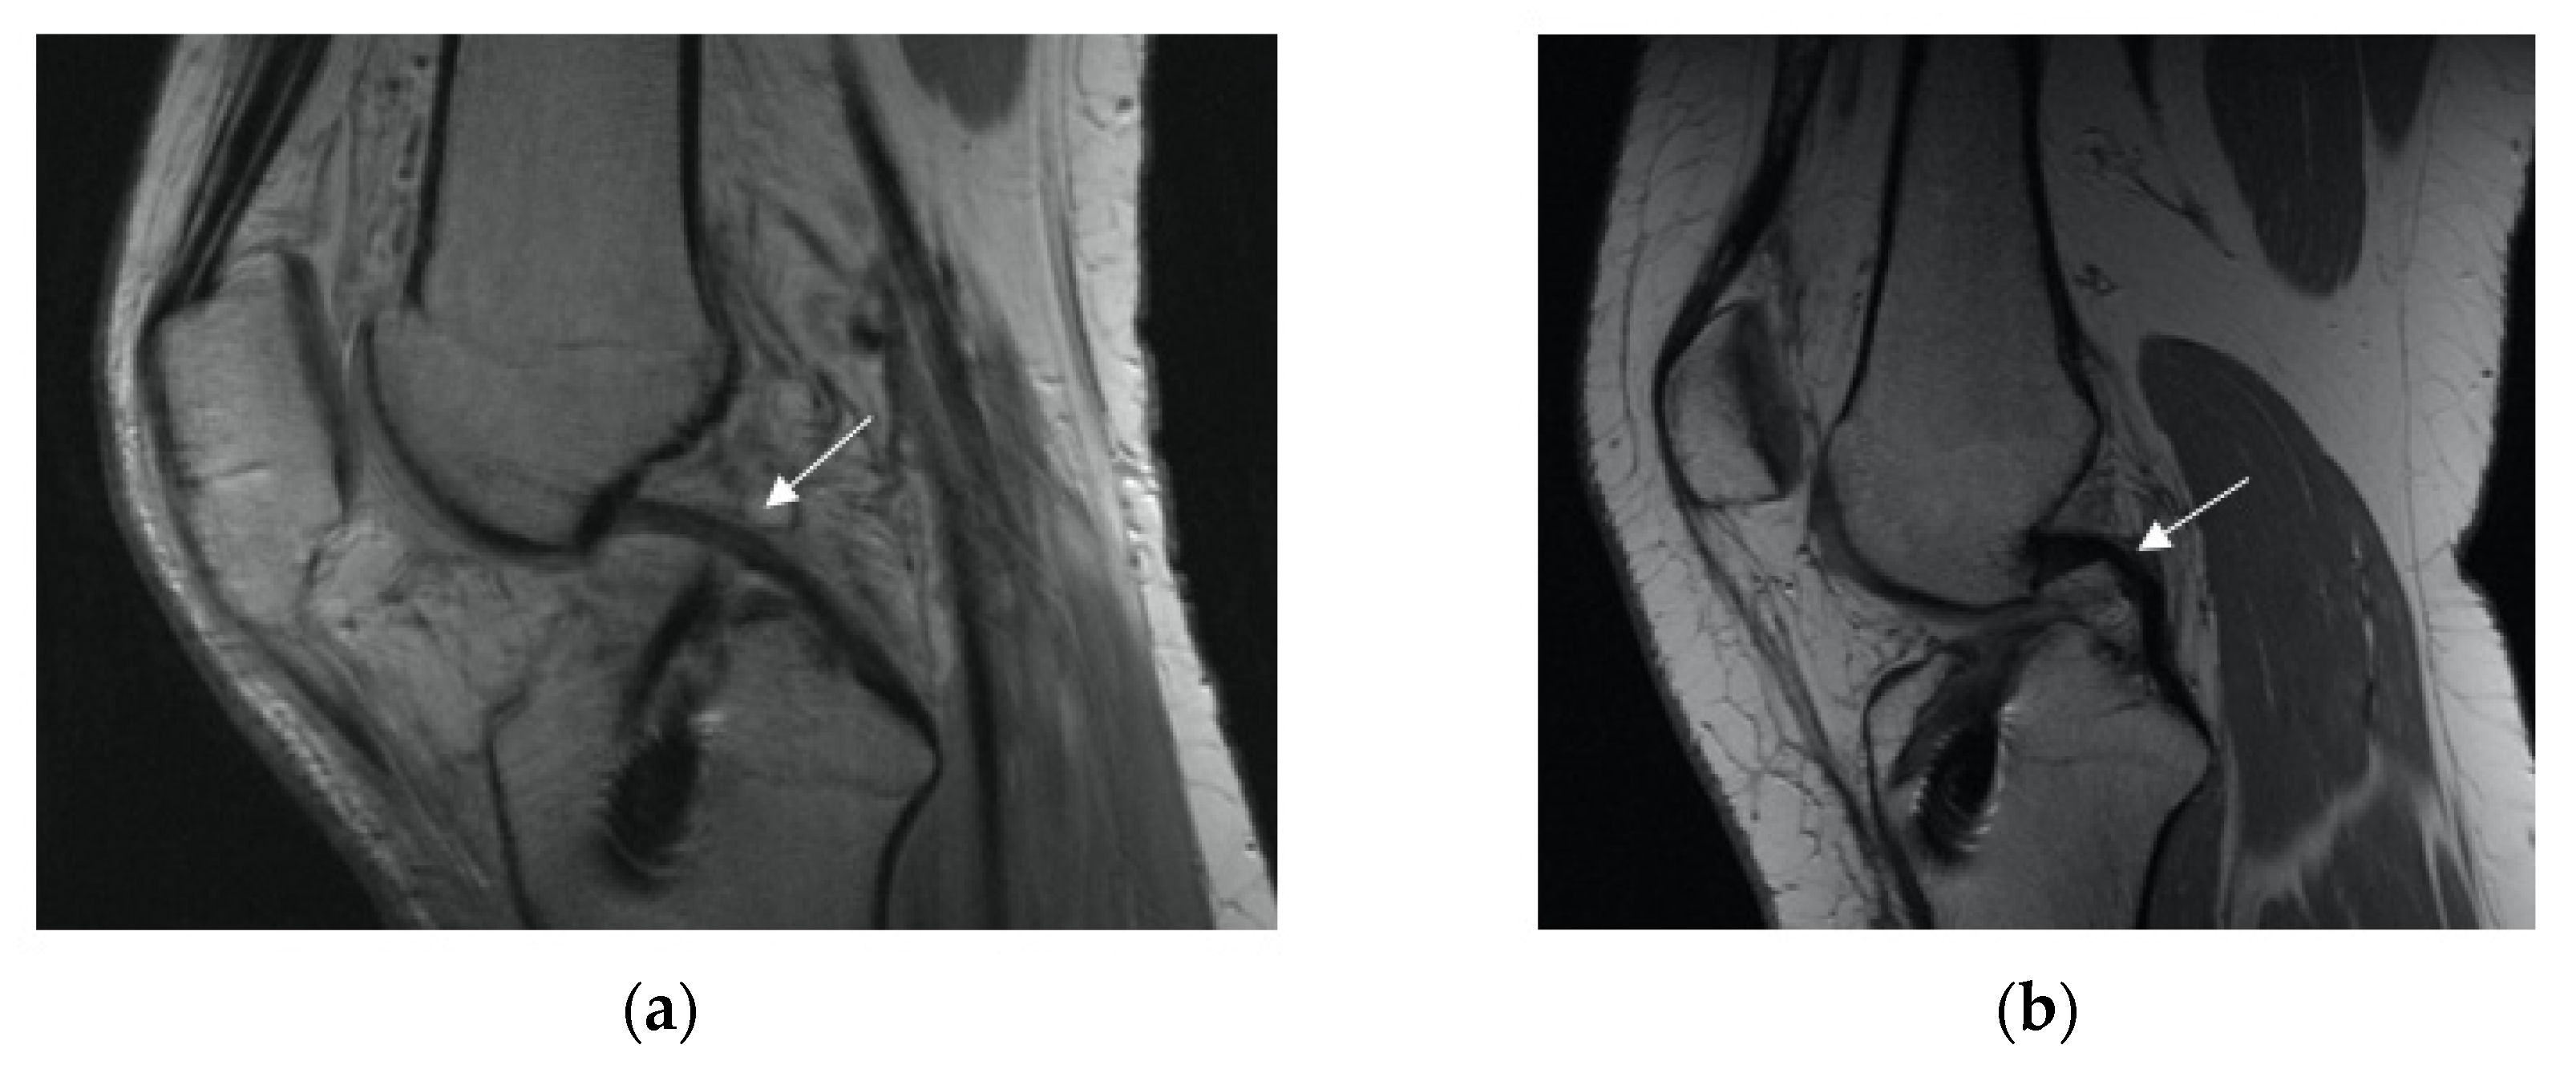

3.2.3. Anterior Tibia Subluxation